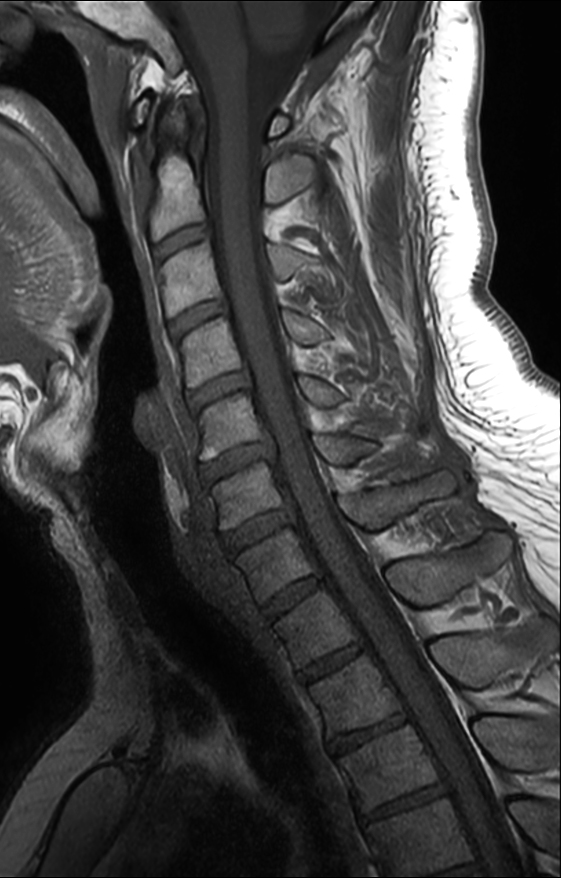

Comprehensive Cervical Spine imaging at 3.0T